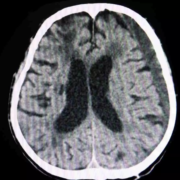

Study Finds No Clear Benefit of Early Surgery Over Conservative Care in Traumatic Acute Subdural Hematoma

Netherlands: A new study published in JAMA Network Open has found that outcomes for patients with traumatic acute subdural hematoma (ASDH) do not significantly differ between those treated in centers favoring early surgical intervention and those preferring conservative management.

Thomas A. Van Essen from the University Neurosurgical Center, Holland, Leiden University Medical Center, Haaglanden Medical Center & Haga, Leiden–The Hague, Netherlands, and colleagues aimed to determine whether an aggressive surgical approach offers better functional recovery compared to conservative management in patients with ASDH following traumatic brain injury (TBI).

The comparative effectiveness analysis included 711 patients from 18 Level 1 trauma centers across the United States who were enrolled between February 2014 and July 2018 as part of the Transforming Research and Clinical Knowledge in Traumatic Brain Injury (TRACK-TBI) study.

The study led to the following findings:

• Researchers observed significant variation across centers in their treatment preferences for acute subdural hematoma (ASDH).

• The proportion of patients undergoing acute surgery ranged from 0% to 86%, with a median of 17%.

• Despite the wide variation in treatment strategies, six-month functional outcomes were similar across centers that preferred early surgery and those that opted for conservative management.

• Out of 711 patients analyzed, 148 (21%) underwent acute cranial surgery, while 563 (79%) received initial conservative management.

• Patients who underwent surgery generally had more severe injuries, reflected by lower Glasgow Coma Scale (GCS) scores and higher rates of pupil abnormalities.

• Among those who had surgery, 87% underwent decompressive craniectomy, and 11% underwent craniotomy.

• In the conservative treatment group, 12% of patients later required delayed surgical intervention.

• Statistical evaluation showed that center-based treatment preference strongly influenced the likelihood of receiving acute surgery.

• However, this variation in treatment approach did not lead to differences in long-term functional outcomes.

• The adjusted common odds ratio for improved outcomes with higher surgical intervention rates was 1.05, indicating no significant benefit of acute surgery over conservative management.

The findings indicate that even with substantial differences in treatment strategies between trauma centers, six-month outcomes for patients with ASDH remained consistent. This suggests that when clinical judgment allows for equipoise—meaning when it is unclear whether surgery or conservative management is superior—conservative treatment may be a reasonable option.

According to the authors, the study highlights the need for further investigation into which subsets of patients might truly benefit from acute surgery, considering variables such as age, neurological status, and comorbid conditions. They recommend future high-quality comparative studies and meta-analyses using patient-level data to strengthen the evidence base for optimal management strategies in traumatic ASDH.

“The large multicenter study underscores that treatment outcomes for traumatic acute subdural hematoma are similar regardless of whether centers favor early surgical intervention or conservative management. For patients in whom neurosurgeons face uncertainty about the need for immediate surgery, initial conservative management may be a safe and appropriate approach,” the authors concluded.